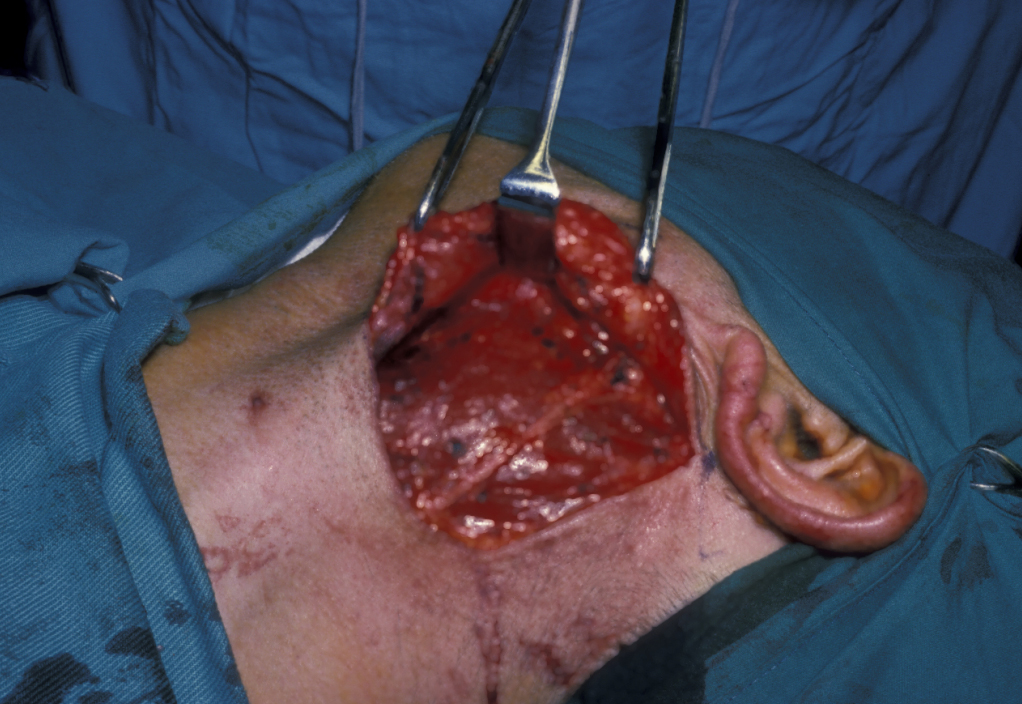

Figure 11: Approach to a large recurrent keratocyst that has grossly distorted the buccal cortex (outward facing cover of mandibular bone).

Figure 12: The involved bone is removed, thus exposing the cyst.

Figure 13: The thick-walled cyst is removed and the surrounding bone is excised.